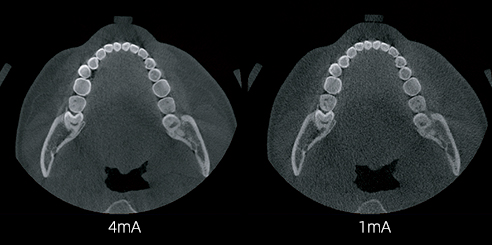

AI + Low-Dose Dental CBCT Technology

- The integrated AI image processor enhances CT quality while reducing radiation exposure.

Consequently, each 3D scan provides superior clarity at a lower dose, ensuring patient safety.